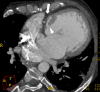

A wide variety of fat-containing entities occur in and near the heart. These findings are often encountered by radiologists and may be incidental or the reason for the patient's clinical presentation. Cross-sectional imaging helps to characterize the extent of these lesions and to formulate a differential diagnosis, which varies by lesion location, imaging features and patient demographics. The purpose of this pictorial essay is to familiarize radiologists with these fat-containing lesions and to help avoid misdiagnosis and errors in management. This pictorial review will discuss the normal fatty structures in and around the heart. A range of common and uncommon fat-containing lesions will then be reviewed based upon lesion location.